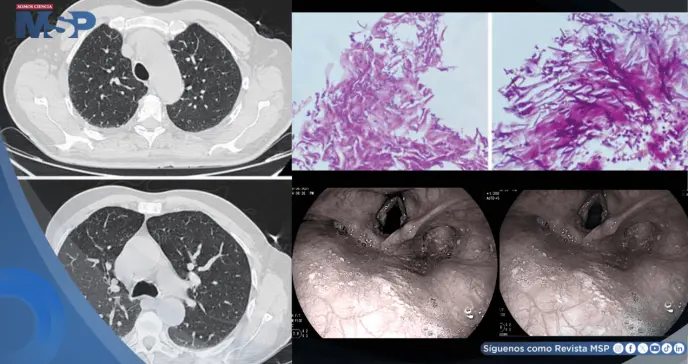

La exploración física reveló sibilancias difusas, pero sin lesiones orales. Los estudios de imagen mostraron un engrosamiento de la pared bronquial, y los análisis de sangre indicaron una marcada inflamación.

Aunque la exacerbación asmática mejoró rápidamente con el tratamiento hospitalario, los síntomas gástricos y la ronquera persistieron. Esta falta de mejoría motivó la realización de una endoscopia digestiva alta. El procedimiento reveló un hallazgo determinante: placas blanquecinas en la orofaringe y una candidiasis esofágica diseminada, con alteraciones asociadas en las cuerdas vocales que explicaban la ronquera crónica.

El análisis histopatológico de las muestras confirmó la presencia de hongos del género Candida.